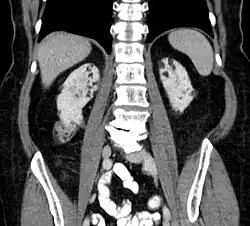

Kidneys

Between 26% and 80% of TSC patients have benign tumors of the kidneys called angiomyolipomas, with hematuria being the most frequent presenting symptom. [8] TSC angiomyolipomas differ from non-TSC angiomyolipomas in age of presentation (31.5 years vs 53.6 years), mean tumor size (8.2 cm vs 4.5 cm), and percentage of cases requiring surgical intervention (50% vs 28%).[8] Although benign, an angiomyolipoma larger than 4 cm is at risk for a potentially catastrophic hemorrhage, either spontaneously or with minimal trauma.

- Repeat MRI of abdomen every one to three years throughout life. Check renal (kidney) function annually. Should angiomyolipoma bleed, this is best treated with embolisation and then corticosteroids. Removal of the kidney (nephrectomy) is strongly to be avoided. An asymptomatic angiomyolipoma that is growing larger than 3 cm is best treated with an mTOR inhibitor drug. Other renal complications spotted by imaging include polycystic kidney disease and renal cell carcinoma.